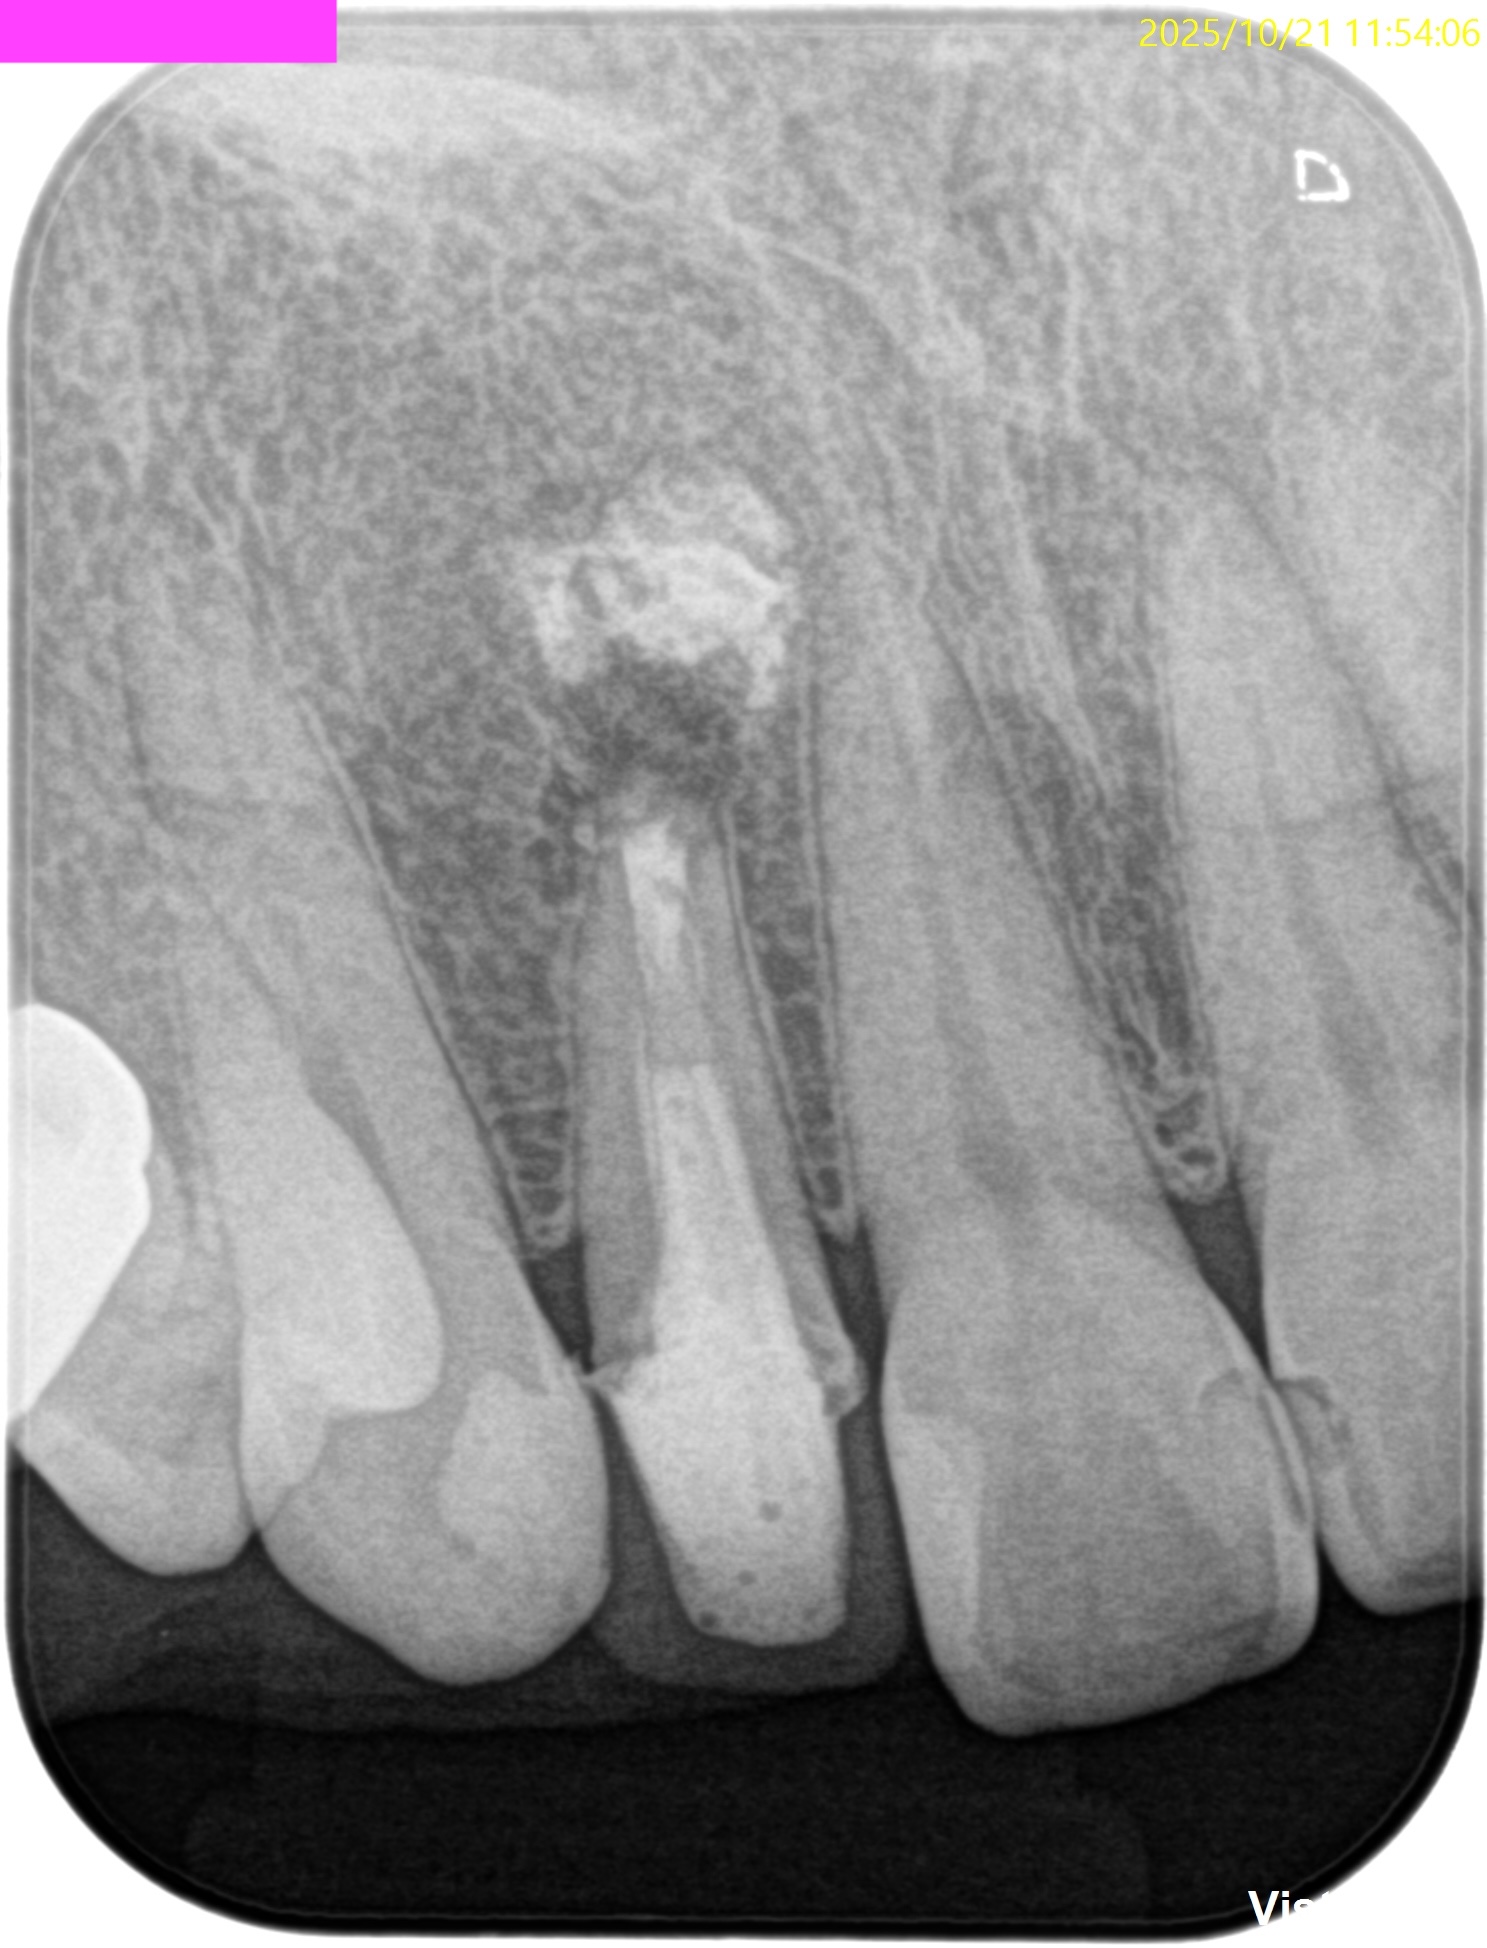

PA(2025.10.21)

何かが根尖から突き出ている。

これが違和感の原因か?と言えば、

違和感の原因はこれではなく、根管の細菌であろう。

もうすでに大きく形成して大きく根充されている以上、再根管治療に勝ち目はない。

そう。Apicoectomyである。